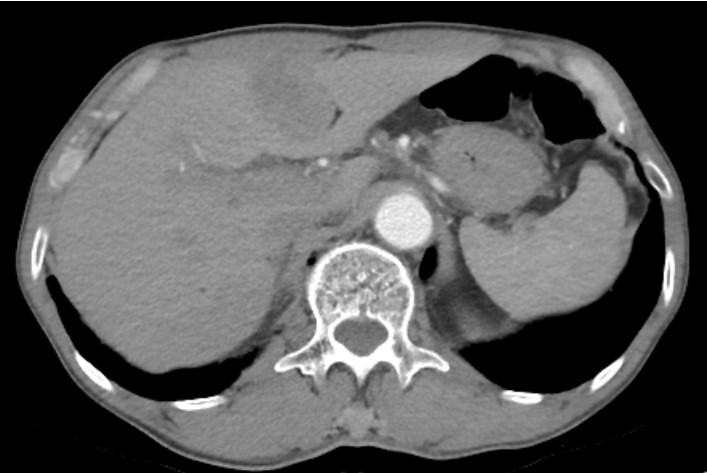

Thời gian gần đây, các bác sĩ của Trung tâm Phẫu thuật Tiêu hóa – Bệnh viện Bạch Mai đã thực hiện thành công ca phẫu thuật cắt gan trái, mở ống mật chủ lấy sỏi cho một bệnh nhân nam 69 tuổi, tiền sử mổ cắt túi mật cách 5 năm, đợt này vào viện với triệu chứng đau bụng âm ỉ thượng vị, da củng mạc mắt vàng, gầy sút 3 kg trong vòng 1 tháng. Bệnh nhân được thăm khám lâm sàng và làm các xét nghiệm cận lâm sàng cần thiết. Kết quả cho thấy: Tình trạng tắc mật do 1 viên sỏi vị trí phần thấp ống mật chủ (OMC) kích thước 12 mm. Bilirubin máu – Một chỉ số đánh giá tình trạng tắc mật tăng gấp 5 lần – 63 mmol/l (giới hạn bình thường là dưới 12 mmol/l). Trên phim chụp cắt lớp vi tính: Vị trí hạ phân thùy (HPT) IV có khối giảm tỷ trọng ngấm thuốc kém kích thước 4×2 cm, không loại trừ một tổn thương ác tính của đường mật. Chất chỉ điểm khối ung thư trước mổ (CA 19-9) tăng nhẹ, sinh thiết khối gan trái trước mổ là tổn thương áp xe, tăng sinh đường mật phản ứng.